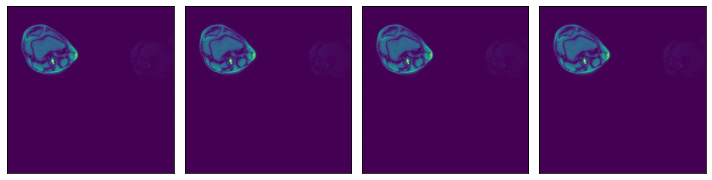

Region-of-interest (ROI) API#

In the example shown above, we see that the relevant data is concentrated in the upper left quadrant of the image and the rest does not contain useful information. This is not true for all the images in the dataset, but it will serve us as a good example to demonstrate ROI reading.

Numpy reader allows the user to specify a region of interest, equivalent to the arguments specified to slice operation. The benefit is that the reader will only read the relevant part of the file, saving I/O bandwidth and memory utilization. Note that setting the dont_use_mmap argument to False will negate that performance benefit, with the entire file being read first and then sliced.

The ROI can be specified in absolute or relative terms, and can be specified on a subset of the array’s axes. For dimensions not specified in the ROI, the whole extent of the array shall be used. For full documentation on ROI decoding, refer to readers.numpy documentation (see arguments roi_start, rel_roi_start, roi_end, rel_roi_end, roi_shape, rel_roi_shape, axes).

Let us see a few practical examples:

ROI start and end, in absolute coordinates#

[9]:

plot_batch(data_roi1)